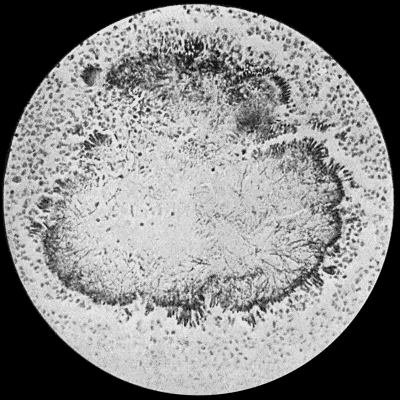

| 30. | Colony of Actinomyces | 126 |

Staphylococcus Aureus.—This is the commonest organism found in localised inflammatory and suppurative conditions. It varies greatly in its virulence, and is found in such widely different conditions as skin pustules, boils, carbuncles, and some acute inflammations of bone. As seen by the microscope it occurs in grape-like clusters, fission of the individual cells taking place irregularly (Fig. 2). When grown in artificial media, the colonies assume an orange-yellow colour—hence the name aureus. It is of high vitality and resists more prolonged exposure to high temperatures than most non-sporing bacteria. It is capable of lying latent in the tissues for long periods, for example, in the marrow of long bones, and of again becoming active and causing a fresh outbreak of suppuration. This organism is widely distributed: it is found on the skin, in the mouth, and in other situations in the body, and as it is present in the dust of the air and on all objects upon which dust has settled, it is a continual source of infection unless means are taken to exclude it from wounds.

Fig. 3.—Streptococci in Pus from an acute abscess in subcutaneous tissue. × 1000 diam. Gram's stain.

Division takes place in one axis, so that chains of varying length are formed (Fig. 3). It is less easily cultivated by artificial media than the staphylococcus; it forms a whitish growth.